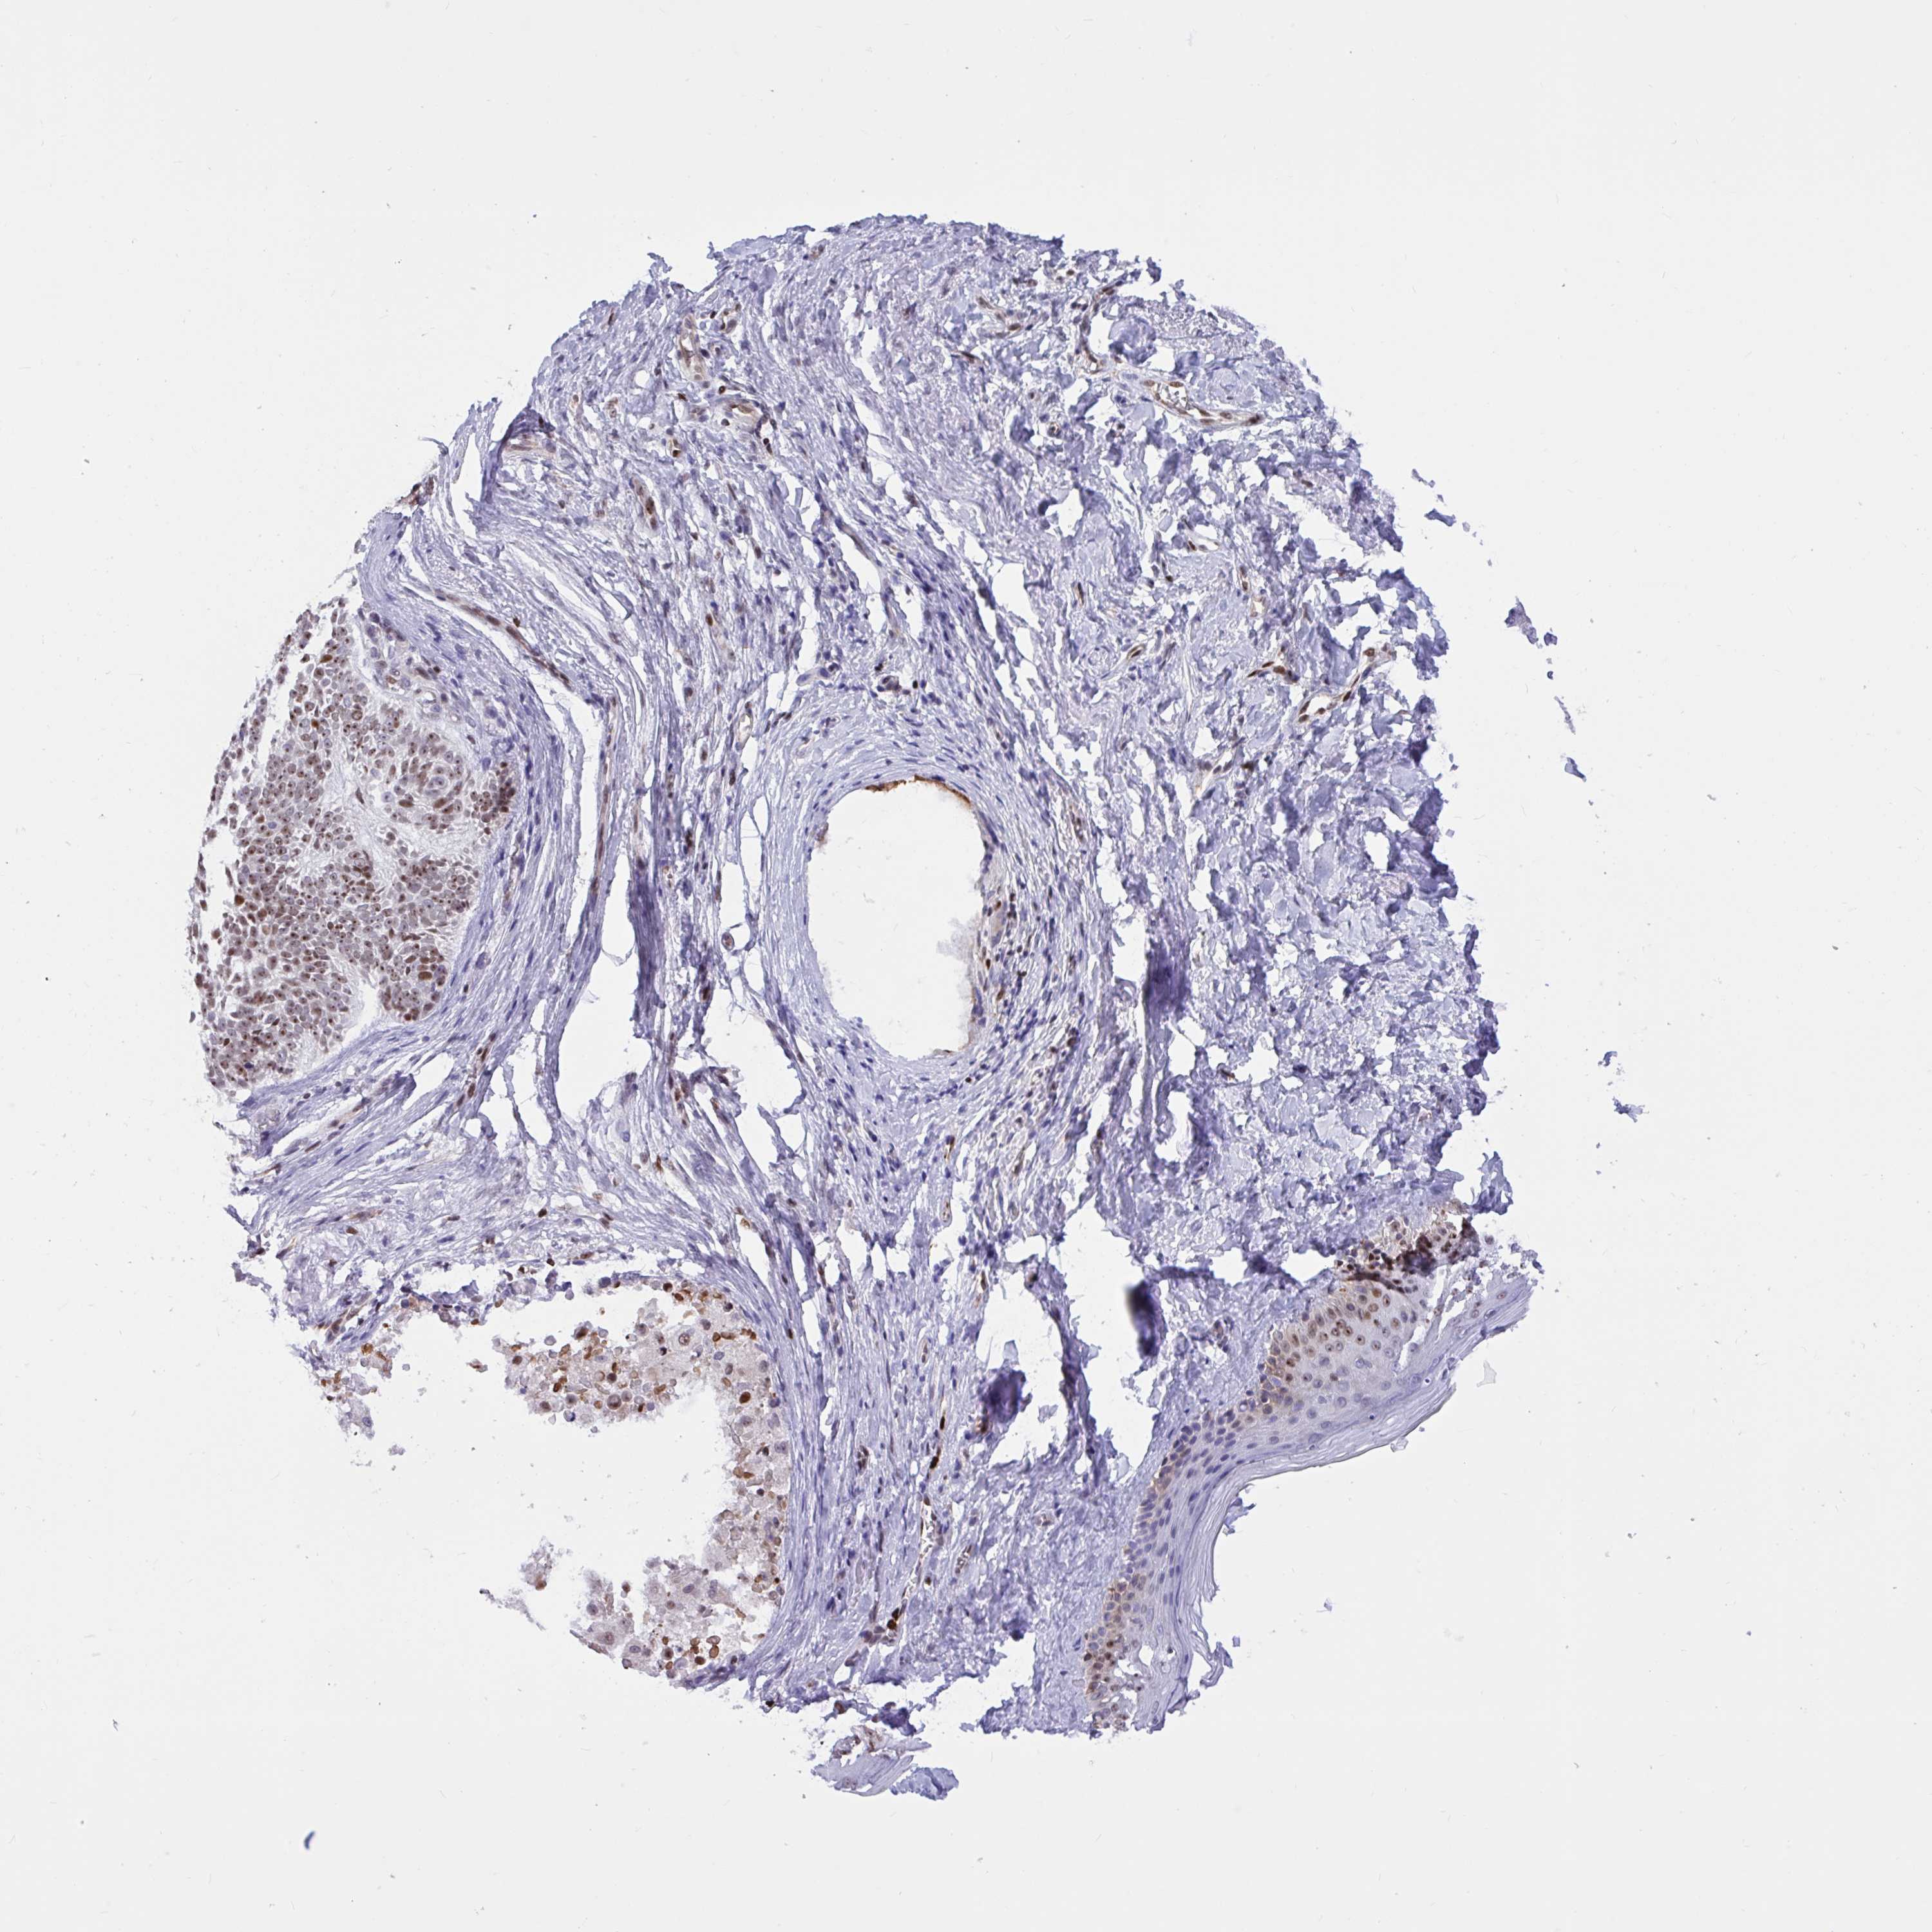

CANCER SKIN CANCER Show tissue menu

Basal cell and squamous cell cancer

SKIN CANCER - Protein expressioni

A mouse-over function shows sample information and annotation data. Click on an image to view it in a full screen mode. Samples can be filtered based on level of antibody staining by selecting one or several of the following categories: high, medium, low and not detected. The assay and annotation is described here.

Each image is clickable and will lead to virtual microscopy that enables deeper exploration of all samples and also displays staining intensity scores, fraction scores and subcellular localization as well as patient and tissue information for each sample.

Antibody HPA003506

Antibody HPA053314

Antibody CAB037206

Squamous cell carcinoma, NOS

Basal cell carcinoma

Squamous cell carcinoma, metastatic, NOS